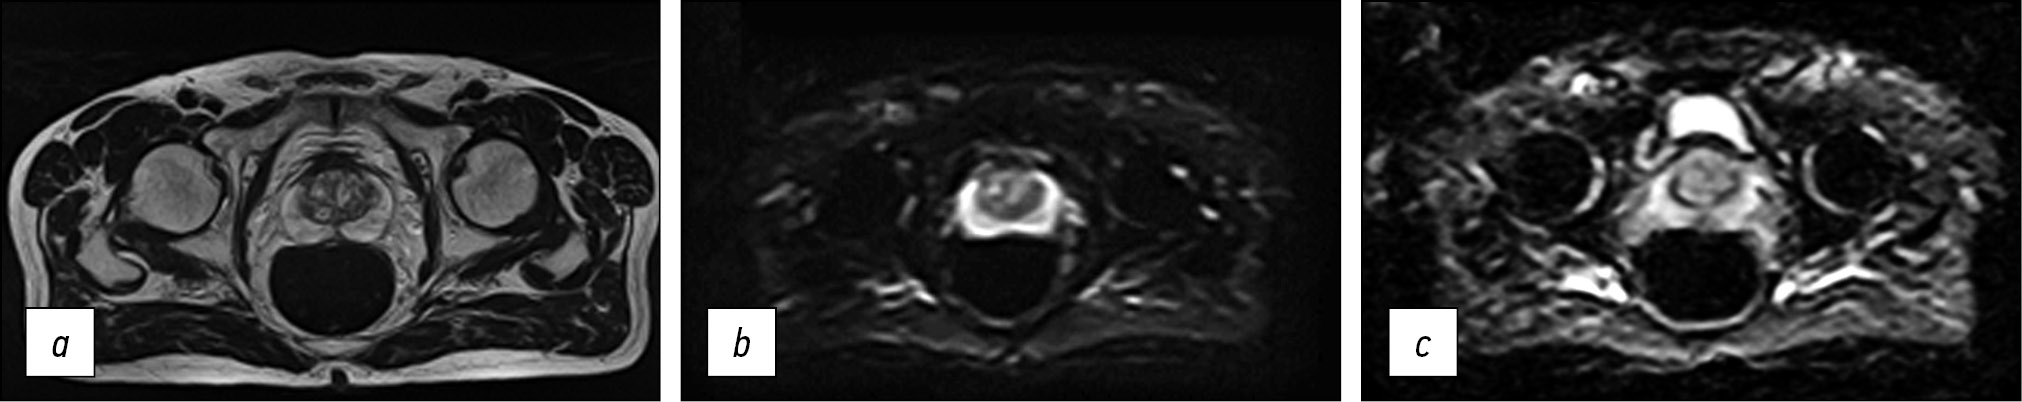

The resulting protocol provides a sufficiently high level of visualization quality. Fig. 5 presents images obtained using the optimized protocol. The total scanning time was less than 11 min.

Fig. 5. Images obtained using the accelerated protocol of biparametric magnetic resonance imaging. Patient with prostate changes consistent with PI-RADS 2: a) T2-WI, axial view; b, c) DWI and ICD.